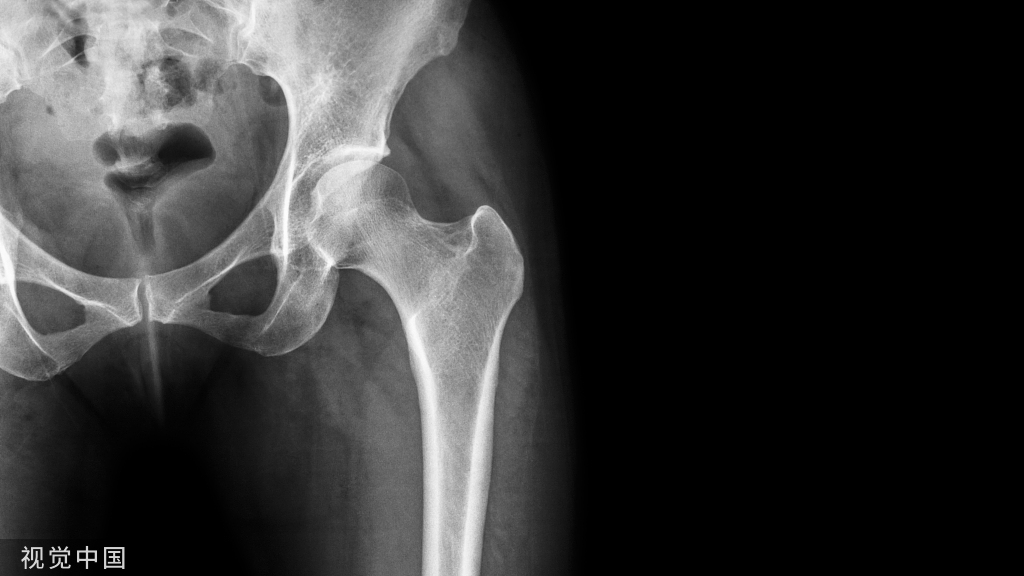

桡桡骨远端骨折是骨科最常见的骨折,桡腕关节和桡尺关节的解剖和生物力学在维持腕部功能和运动中起着关键作用。与这些骨折相关的问题,包括妨碍握力和腕关节不稳定的早期关节炎。桡骨远端骨折最常见的治疗方法是采用石膏固定闭合复位。但并发症如骨折畸形愈合和尺桡关节远端半脱位。

开放性手术创伤较大,闭合复位经皮内固定具有创伤小,恢复快,花费少等优点,下面就介绍一种经皮穿针方法。

首先进行闭合复位,在透视机监护下以确认复位满意,然后按以下顺序进行骨折固定: